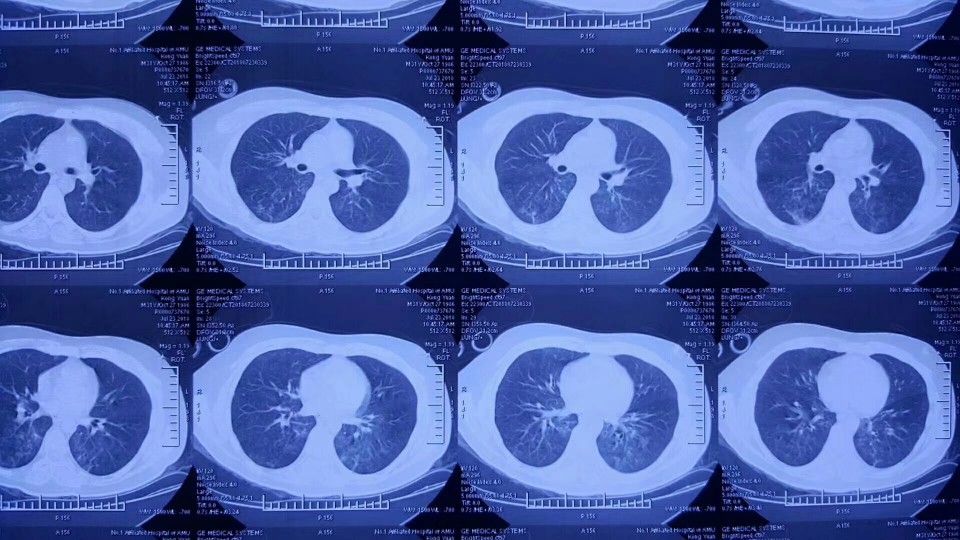

小孔入住当地医院ICU后病情仍在迅速恶化,持续深昏迷,并出现多脏器功能衰竭。2天后,当地市医院ICU与我院急诊科联系,小孔被转入我院EICU,此时的小孔深昏迷状态(格拉斯哥评分3分)、急性呼吸窘迫综合征、肾衰无尿、休克,止凝血功能障碍。EICU团队迅速展开各项抢救措施——有创血流动力学(PiCCO)监测、全身亚低温、呼吸机通气、床旁肾脏替代……,眼看着呼吸支持条件已很高,氧合仍无法维持,全身缺氧状态无法纠正,小孔病情继续恶化。